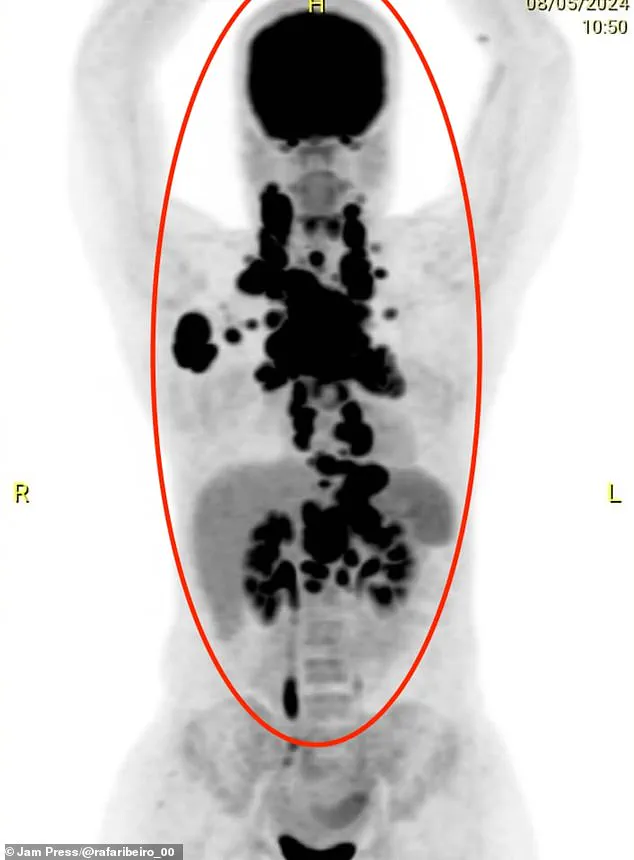

Scans finally revealed the grim truth: her upper body was riddled with tumours, which were compressing her oesophagus and threatening to take over her heart. 'The tumours were crushing me from the inside,' she said. 'My heart felt like it was being taken over, but it was just the pressure from the tumours.' The diagnosis of B-cell non-Hodgkin lymphoma—a form of cancer that typically starts in the lymph nodes—was both shocking and devastating.